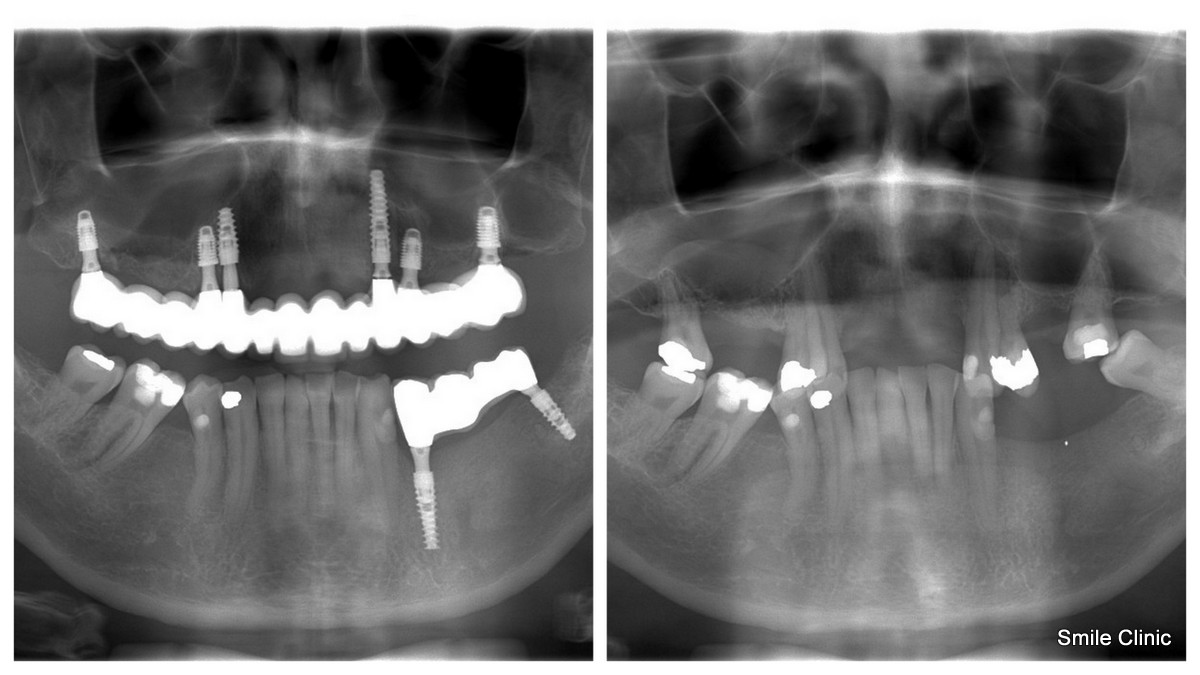

He had been wearing false upper teeth for some time, and decided to finally get rid of it by opting for the “all on 6” dental implant procedure giving him 12 new, fixed teeth for his upper jaw on 6 dental implants, as well as a crown tooth bridge of 4 teeth for the bottom jaw towards the back for added eating strength.